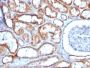

This MAb recognizes a 60 kDa antigen associated with the mitochondria in human cells. It can be used to stain mitochondria in cell or tissue preparations and can be used as a mitochondrial marker in subcellular fractions. It produces a spaghetti-like pattern in normal and malignant cells. This antibody is an excellent marker for human cells in xenographic model research. It reacts specifically with human cells, including neurons and embryonic stem cells. Immunostaining pattern with anti-mitochondrial MAb has been reported as a useful discriminatory adjunct in the complex differential diagnosis of granular renal cell tumors. Reportedly, this MAb facilitates the classification of salivary tumors.Primary antibodies are available purified, or with a selection of fluorescent CF® Dyes and other labels. CF® Dyes offer exceptional brightness and photostability. Note: Conjugates of blue fluorescent dyes like CF®405S and CF®405M are not recommended for detecting low abundance targets, because blue dyes have lower fluorescence and can give higher non-specific background than other dye colors.

HeLa or HepG2 cells. Hepatic carcinoma.

IF (verified)|IHC, FFPE (verified)|WB (verified)

Higher concentration may be required for direct detection using primary antibody conjugates than for indirect detection with secondary antibody|Does not react with mouse or rat, others not known|Immunohistology formalin-fixed 0.5-1 ug/mL|Staining of formalin-fixed tissues requires boiling tissue sections in 10 mM Tris with 1 mM EDTA, pH 9.0, for 10-20 min followed by cooling at RT for 20 minutes|Immunofluorescence (PFA- or MeOH-fixed) 0.5-1 ug/mL|Optimal dilution for a specific application should be determined by user